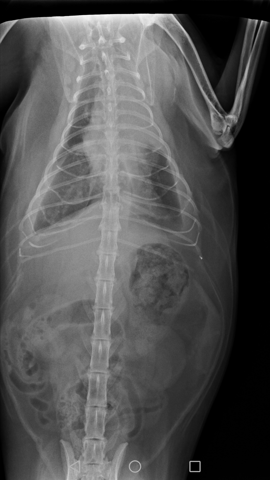

Bonjour, voilà la radio pulmonaire de mon chat de 12 ans, le vétérinaire hésite entre cardiomégalie ou tumeur proche du cœur. Un scanner à un coût important et ma minette est dyspnéique ce qui est incompatible avec une anesthésie, les oreillettes sont d'une taille limite supérieure selon ses dire. Il lui a donné un diurétique pour évacuer l'épanchement. Et des comprimés pour le cœur. J'ai peur de payer des frais importants alors que c'est peut être un cancer pour lequel on ne peut rien faire sinon palier aux symptômes. Si vous vous y connaissez pouvez vous me donner votre avis ? Tumeur ou pas de tumeur svp ?

Épanchement pleural cause cardiaque ou cancer

Merci pour votre témoignage, le problème des vétérinaires est qu'ils sont également commerçants. Comme je l'ai écrit précédemment il n'est pas sûr du diagnostic. J'ai donc posté la radio au cas où quelqu'un qui s'y connaisse pourrait m'aider.. Voir s'il y a une tumeur ou si c'est le cœur qui est gros.. Ce qui change tout. Je suis vraiment désolée pour votre chat. J'espère ne pas être obligée d'en arriver là.

Il avait une importante quantité d'eau dans les poumons. Un prélèvement du liquide a été fait pour biopsie, dont l'analyse a montré que c'était cancéreux. Cet examen est assez peu onéreux et moins invasif que d'autres, pas vraiment douloureux selon la véto.